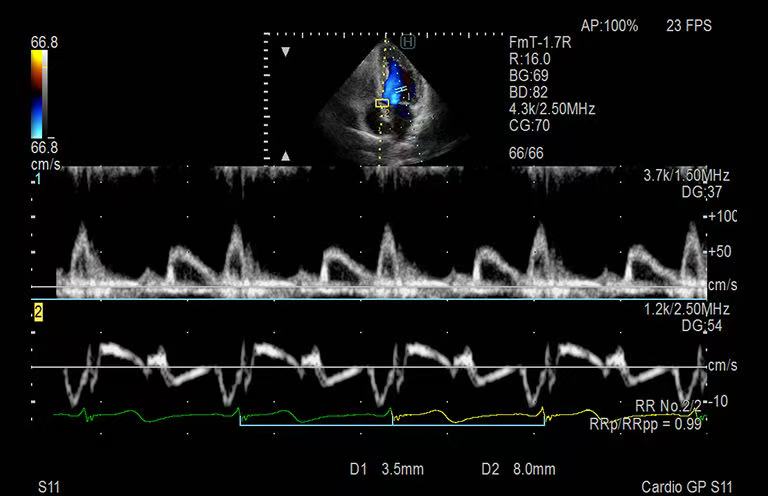

心臓エコー画像(出典:FUJIFILM)

一方、心臓エコーは、①問診、②診察、③心電図で異常を認めた場合に、精密検査として行うことが大半です。

具体的な適応としては、①問診で、胸痛や動悸、心臓疾患の家族歴がある方などです。心臓の一部に動きの悪化を見つけることで、冠動脈(栄養血管)の狭窄を疑ったり、心機能異常がないかを確認します。

②診察で、心雑音を認める方(受診者の1%の方)が良い適応です。心臓弁の逆流や狭窄、先天的な構造異常の有無をみます。